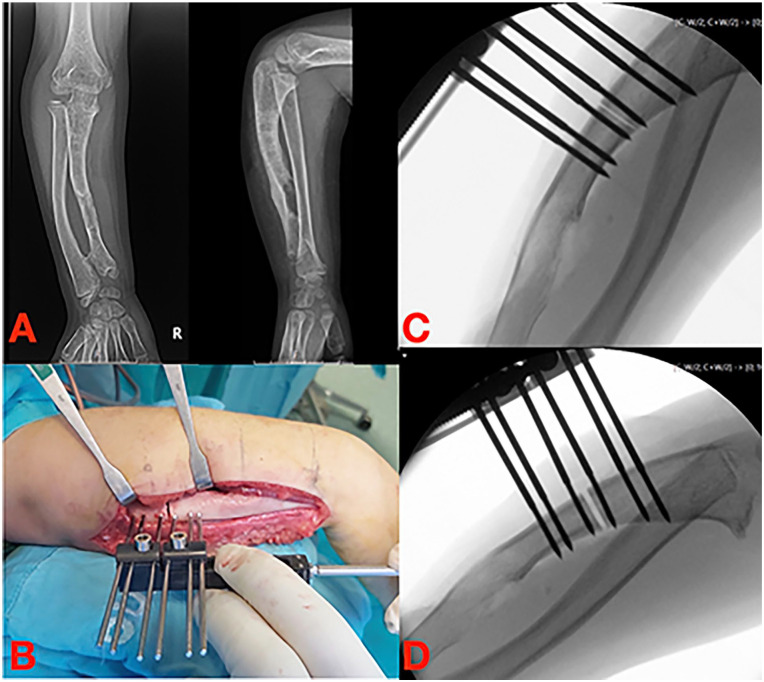

使用外固定架是骨科医生治疗许多临床疾病的文化背景的一部分。多年来,固定架的设计和生物力学知识导致了不同的解决方案和技术,骨延长及其更好的理解与外固定架的发展和牵张成骨生物学原理的应用一起出现。作者对儿童上肢使用外固定架和延长系统进行了文献综述。尽管外固定架在上肢的应用比下肢的应用要有限得多,但有外伤、先天性、肿瘤和感染性病因的迹象。然而,尽管钢板、螺钉和髓内延长钉的新系统得到了广泛应用,但何时使用外固定的问题仍未得到解决。另一个争论点是使用单侧或圆形框架肱骨延长和纠正前臂畸形的多发性遗传性外骨骼疾病(MHE)或桡骨纵向缺陷后遗症。单轴固定架在所有检查区域的骨骼延长中都保持着突出的作用,尽管其作用可能被机动髓内钉所超越,特别是在肱骨延长方面。六足系统可能代表了未来多平面前臂畸形的矫正;然而,为了更好地验证其应用和优势,需要在更大的系列上进行多中心研究。

The use of external fixators is part of the cultural background of orthopedic surgeons in treating numerous clinical conditions. Over the years, fixator design and biomechanical knowledge have led to different solutions and techniques, and bone lengthening and its better understanding come together with the development of external fixators and the application of the biological principle of distraction osteogenesis. The authors conducted a literature review about using external fixators and lengthening systems in pediatric upper limbs. Despite the applications of external fixators in upper limbs remaining much more limited than those of the lower limbs, there are indications of traumatic, congenital, tumor, and infectious etiologies. However, despite the spread of new systems of plate and screws and intramedullary lengthening nails, the problems about when to use external fixation remain unsolved. Another debated point is about using monolateral or circular frames for humeral lengthening and the correction of forearm deformities in multiple hereditary exostoses disease (MHE) or radial longitudinal deficiency sequelae. Monoaxial fixators retain a prominent role for skeletal lengthening in all the districts examined, although their role could be outclassed by the motorized intramedullary nails, especially for humeral lengthening. Hexapod systems are likely to represent the future for the correction of multiplanar forearm deformities; however, multicenter studies on larger series will be necessary to better validate their applications and advantages.